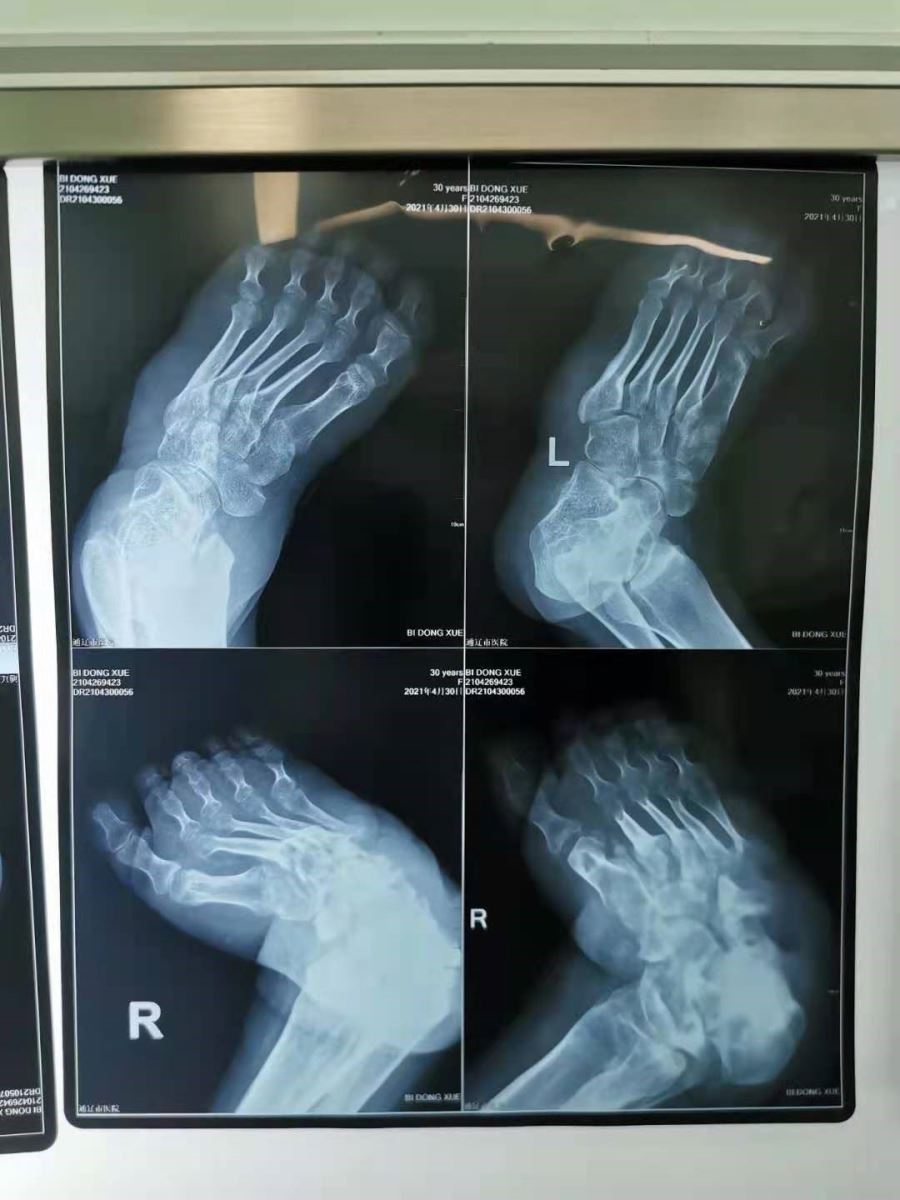

患者女性,32岁,患有严重的双侧马蹄内翻足,由于家庭经济困难,一直未做矫形手术导致长期行走不便,足部外侧皮肤反复溃疡,严重影响了日常生活。骨五科曲志强医师接诊后,每天为患者的双重足部溃疡换药,抗炎治疗两周后,炎症反应得到控制,伤口逐步愈合,病情得到缓解,但如果只进行保守治疗并不能从根本上治愈患者,其日后仍会行走不便。因此,患者及家属强烈要求进行矫形手术。既往我院足踝矫形手术经验较少,并且该患者双侧足畸形的严重程度不同,左侧足畸形较轻,仅有轻度的跖屈内翻畸形,右侧畸形较重,整个足处于跖屈和内翻的位置伴前足内收及弓形足畸形,矫形手术难度较大,需多种手术方式联合施治,这也增加了治疗难度。

胡中申主任带领团队术前从多个角度评估,最终设计出严格的手术方案及备选方案:左足手术方式包括跟腱松解延长术、跖筋膜松解术、胫骨前肌腱外移术。右足手术方式包括跟腱延长术、内后方关节囊切开术、跟骨截骨外移术、三关节融合术等。经过近3个小时的共同努力,手术顺利完成。术后患者恢复良好,大大缩短了住院及康复时间。